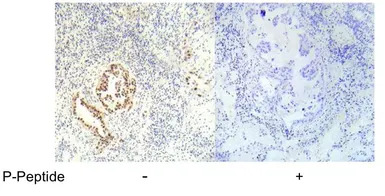

IHC-P analysis of human lung carcinoma tissue using GTX79021 LKB1 (phospho Ser334) antibody.

Absorption Control in Immunohistochemistry Using Phospho-Peptides Immobilized on Magnetic Beads

neutralization of phospho-specific antibodies with phospho-peptides immobilized on magnetic beads. This technique allows for sequestration of antibody–peptide complex from the incubation solution, minimizing the risk of formation of unblocked antibodies capable